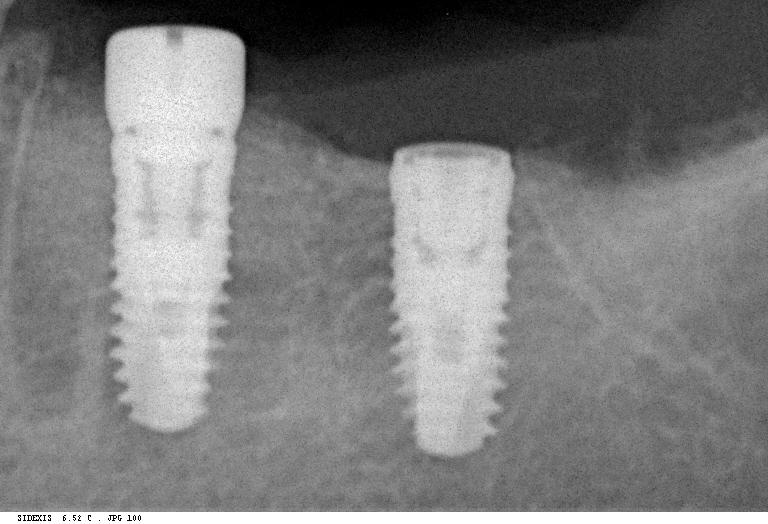

Прицельный радиовизиографический снимок можно сделать в любой из наших клиник. В отличие от обычных прицельных рентгенограмм зубов, доза лучевой нагрузки при проведении подобного исследования в несколько раз ниже, поэтому таких снимков можно сделать очень много. Например, по существующим стандартам, терапевт стоматолог может сделать до десяти снимком зуба в процессе эндодонтического лечения — и это, разумеется, необходимо для качественного лечения каналов зубов.

В хирургической практике я использую прицельные снимки как для первичной диагностики: например, чтобы быстро понять локализацию ретинированного зуба мудрости и его отношение к окружающим структурам, либо для интра- и послеоперационного контроля результатов имплантологического лечения. А наличие цифровой базы радиовизиографических снимков позволяет понять, как ведет себя протез на импланте в течение длительного времени: